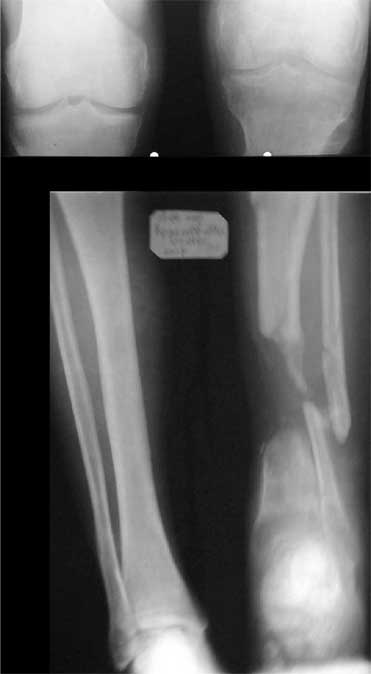

Dorogie kollegy,Have a nice day,Ja bi hotil obsuzdat' s Vami dvuh bolnih, kotorie postupili segodnjia ko mene. Pervy iz nih (OI) bolnoi s otkritoi tiazeloi mehanicheskoi travmoi Rt. leg segment v rezultate DTP, ot chego on imeet sledueshie povrezdenjia:- Otkrity perelom kostei pravoi goleny v srednei i niznoi ee trety s poteriem okolo 10 cm. kostnogo veshestva ot bolshebersovoi kosty, - Povrezdenjia a.tibialis post. s massivnim povrezdeniem zadneoi gruppy musculs goleny,- Malobersovjia kost' imeet segmentarny perelom, ee nizny fragment (kak Vi videte na foto) vistupaet na kozy okolo VNUTRENNOI Lodizky! - Traumaticheski Shock 2-3Drugih povrezdenjia net.

Nemedlenno bolnoi bil' intubirovan i provedeny vse protivoshokovie procedury, pravjia golen' bila pomeshenjia na apparat' Storm, dla reduksii kostei posle ee fiksasii k apparatu s pomoshio 2 spitsy 3mm D. Provedena Repozitsia pereloma i fiksirovana STORMOM vremenno, za tem sosudisty hirurg vypolnil 2 obhodnih anastomosa for a. Tibilis posterior, bili udaleny bolshie chasty iz musculov zadnoi gruppy goleny v predelah "vozmozno vedemih" zdorovoi tkany, oblast' pereloma promita by N. sol. 0.9% - 12 L. Zatem byla proizvedena okonchatenjia reduksia pereloma posle umerennoi traksii goleny na apparate, i fiksasiya pereloma s pomoshio apparata vneshnei fiksasii. Tak, Kakie soobrazanjia po dalneshemu vvdenjia bolnogo? On poluchaet antibiotiky i bolshie dozy LMH (Clexane 80 X 2) i vse ostalnoe......

1. Chto kasaetsa snimkov bolnogo to oni budut segodnjia v horoshim digital forme,

5. Ne tolko zadnjia poverhnost' otkritajia, est' chast' kosty na protezenjii okolo 4-h cm. obnazena po peredne-vnutrennoi poverhnoste Prox. kones tibia".